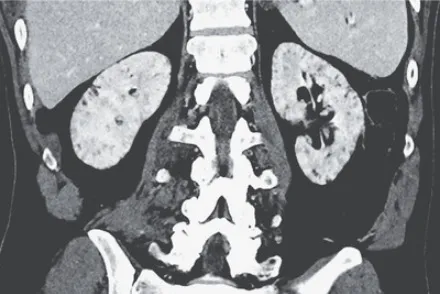

IRA + Icterícia: Um Caso que Exige Investigação Detalhada